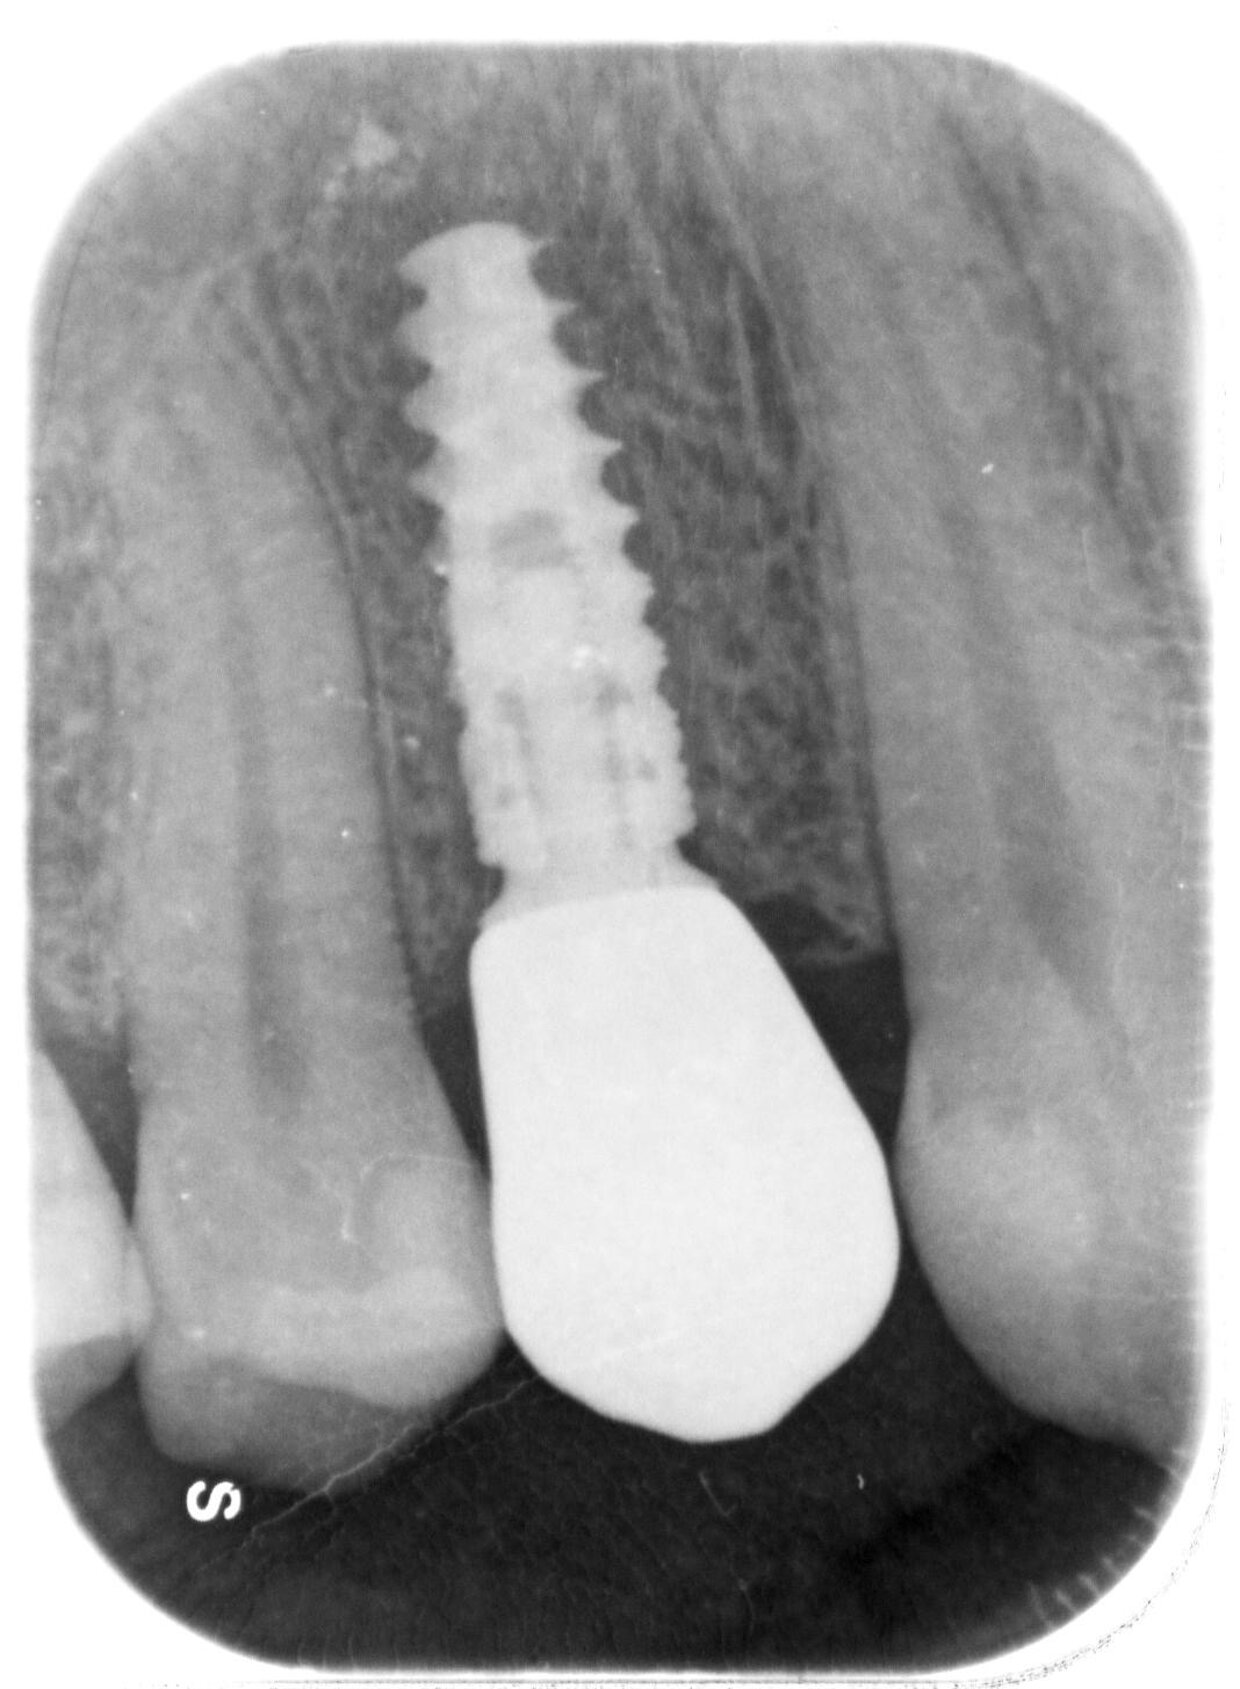

Il posizionamento degli impianti è stato pianificato prima dell'intervento su un software dedicato. In un'unica seduta, dopo l'estrazione degli elementi dentari compromessi, sono stati immediatamente inseriti gli impianti nella posizione pianificata, grazie alla realizzazione della dima chirurgica. Per ridurre il riassorbimento osseo a lungo termine e garantire quindi una maggiore resa estetica (vista la zona d'intervento), la chirurgia è stata eseguita con una particolare tecnica denominata: Socket Shield Technique.